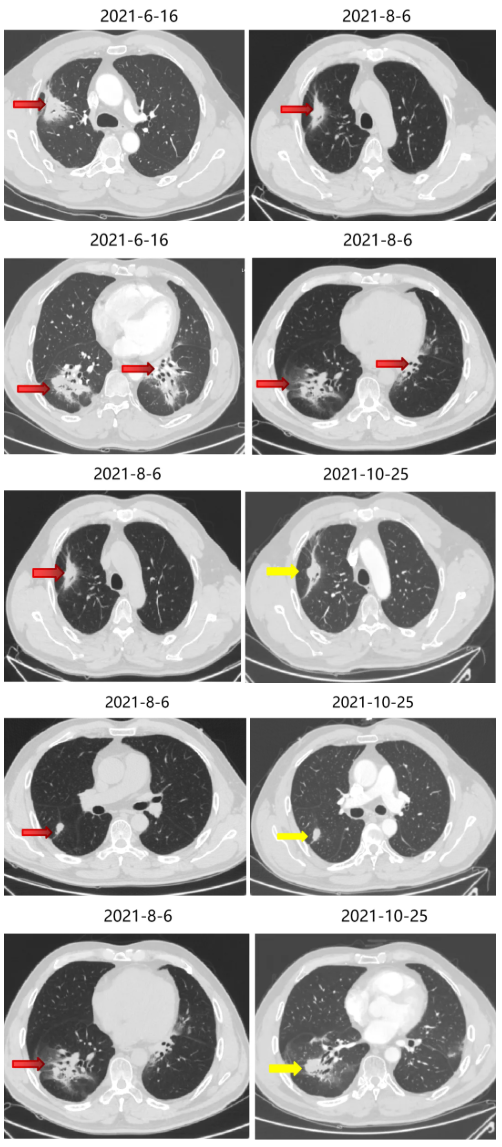

2018-10-11 胸部CT:双肺转移瘤较前进展。

2、4周期化疗后疗效评价PR。

局部治疗(一):射频消融治疗

2019-4至2019-6 外院行肺内转移瘤(6处)射频消融治疗。

局部治疗(二):SBRT治疗

2020-11-6至2020-11-25 左肺下叶及右肺下叶转移灶放疗:95% PTV1-2 74.7Gy/4.98Gy/15F。

2020-12-31至2021-1-19右肺上叶转移灶放疗:95% PTV 74.7Gy/4.98Gy/15F。

SBRT疗效评价:部分缩小。

期间2021-3-15胸部CT:双肺转移瘤部分较前略增大,疗效SD。

三线治疗疗效评价:部分增大,PD。

2021-6-17 起口服曲氟尿苷替匹嘧啶片(TAS-102)40mg bid。

四线治疗疗效:部分略减小,SD。

2021-10-29、2021-11-1 行CT引导下双肺转移灶放射性碘125粒子植入术。

继续曲氟尿苷替匹嘧啶片(TAS-102)40mg bid+瑞戈非尼40mg qd(2021-11始)至今。

五线治疗疗效:病灶控制良好。

2022-4-13、2022-4-15 行CT引导下双肺转移灶放射性碘125粒子植入术。